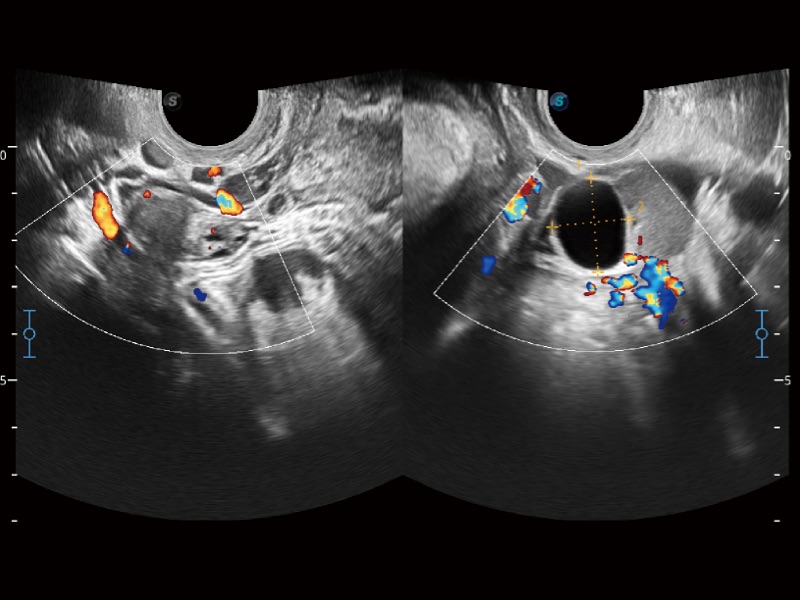

高分辨率血流成像技术提高了对低速血流信号的检测能力。在提高空间分辨率的同时,也克服了血流外溢现象,为用户提供更加真实的血流动力学信息。

妇产科应用